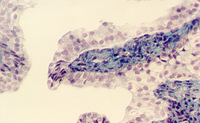

Stratified Columnar epithelium is rare. One place you can find it is in the largest ducts of salivary glands (parotid, submandibular, etc). The basal layer of cells are cuboidal cells and the layer nearest the apical surface includes columnar cells. The large droplets are mucus, in Goblet cells. This also illustrates the fact that epithelia are classified according to the cells nearest the lumen, in this case columnar.

Below is another view of a large (excretory) duct of a salivary gland showing the mucin in Goblet cells after a special stain. What might be the advantages of an epithelium that has a basal cuboidal cell layer and an apical columnar cell layer?